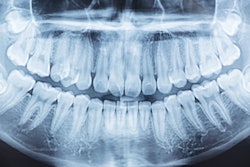

The tool is powered by artificial intelligence and measures interproximal radiographic bone levels to assess the presence of gum disease. Perio Assist, which can be used in patients age 12 and older, supports clinicians' periodontal probing findings to aid in the early identification of some systemic diseases.